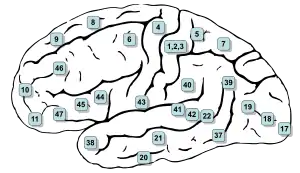

Brodmann area 4 of human brain. | |

Brodmann area 4 refers to the primary motor cortex of the human brain. It is located in the posterior portion of the frontal lobe.

Brodmann area 4 is part of the precentral gyrus. The borders of this area are: the precentral sulcus in front (anteriorly), the medial longitudinal fissure at the top (medially), the central sulcus in back (posteriorly), and the lateral sulcus along the bottom (laterally).

This area of cortex, as shown by Wilder Penfield and others, has the pattern of a homunculus. That is, the legs and trunk fold over the midline; the arms and hands are along the middle of the area shown here; and the face is near the bottom of the figure. Because Brodmann area 4 is in the same general location as primary motor cortex, the homunculus here is called the motor homunculus.